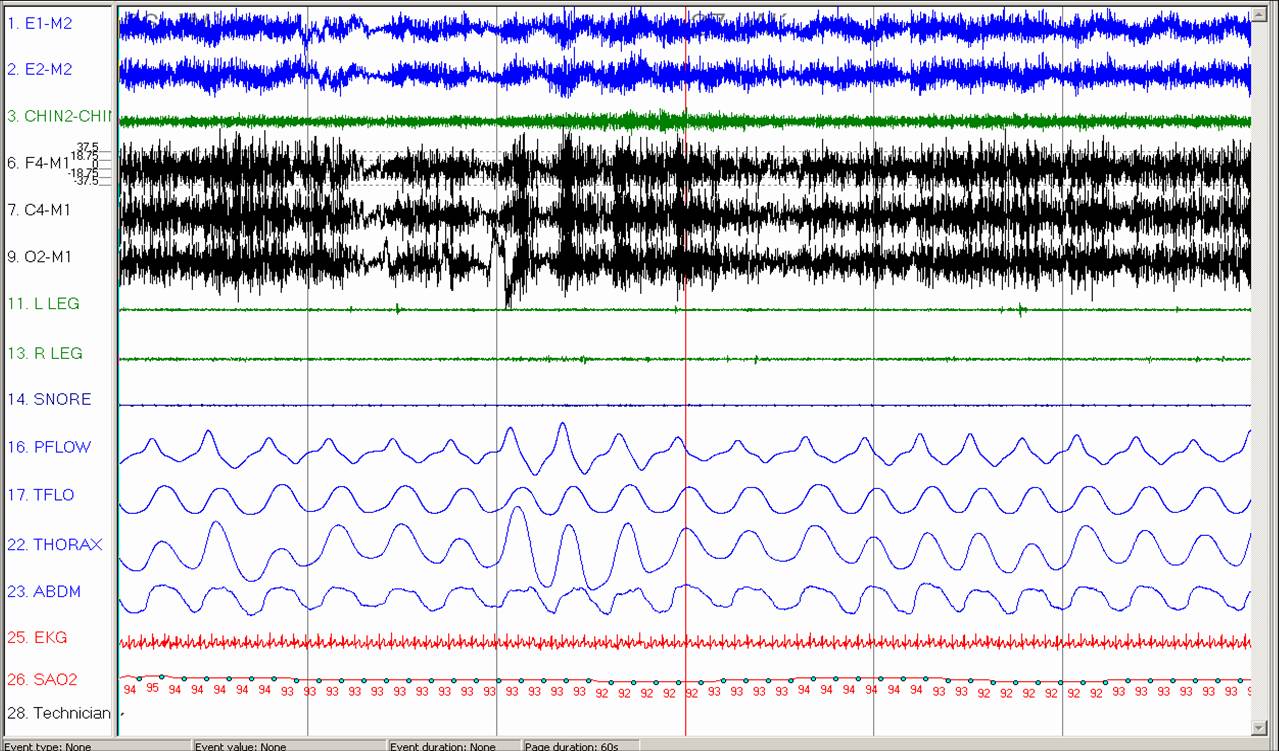

- The first fragment shows a 1 minute segment of wakefulness; the second fragment shows a 1 minute segment of stable Stage N3 sleep.

In the first fragment during wakefulness, the thorax and abdomen are moving in synchrony (blue double arrows) while during Stage N3 sleep (second fragment, green double arrows), the thorax and abdomen are moving paradoxically and there is oxyhemoglobin desaturation to 88%.

This finding is consistent with diaphragm dysfunction.

In addition to the paradoxical breathing shown, the patient exhibited severe obstructive sleep apnea with AHI 30/hr; all of the respiratory events were hypopneas and were primarily in the supine position and during transitions between wakefulness and N1 sleep.